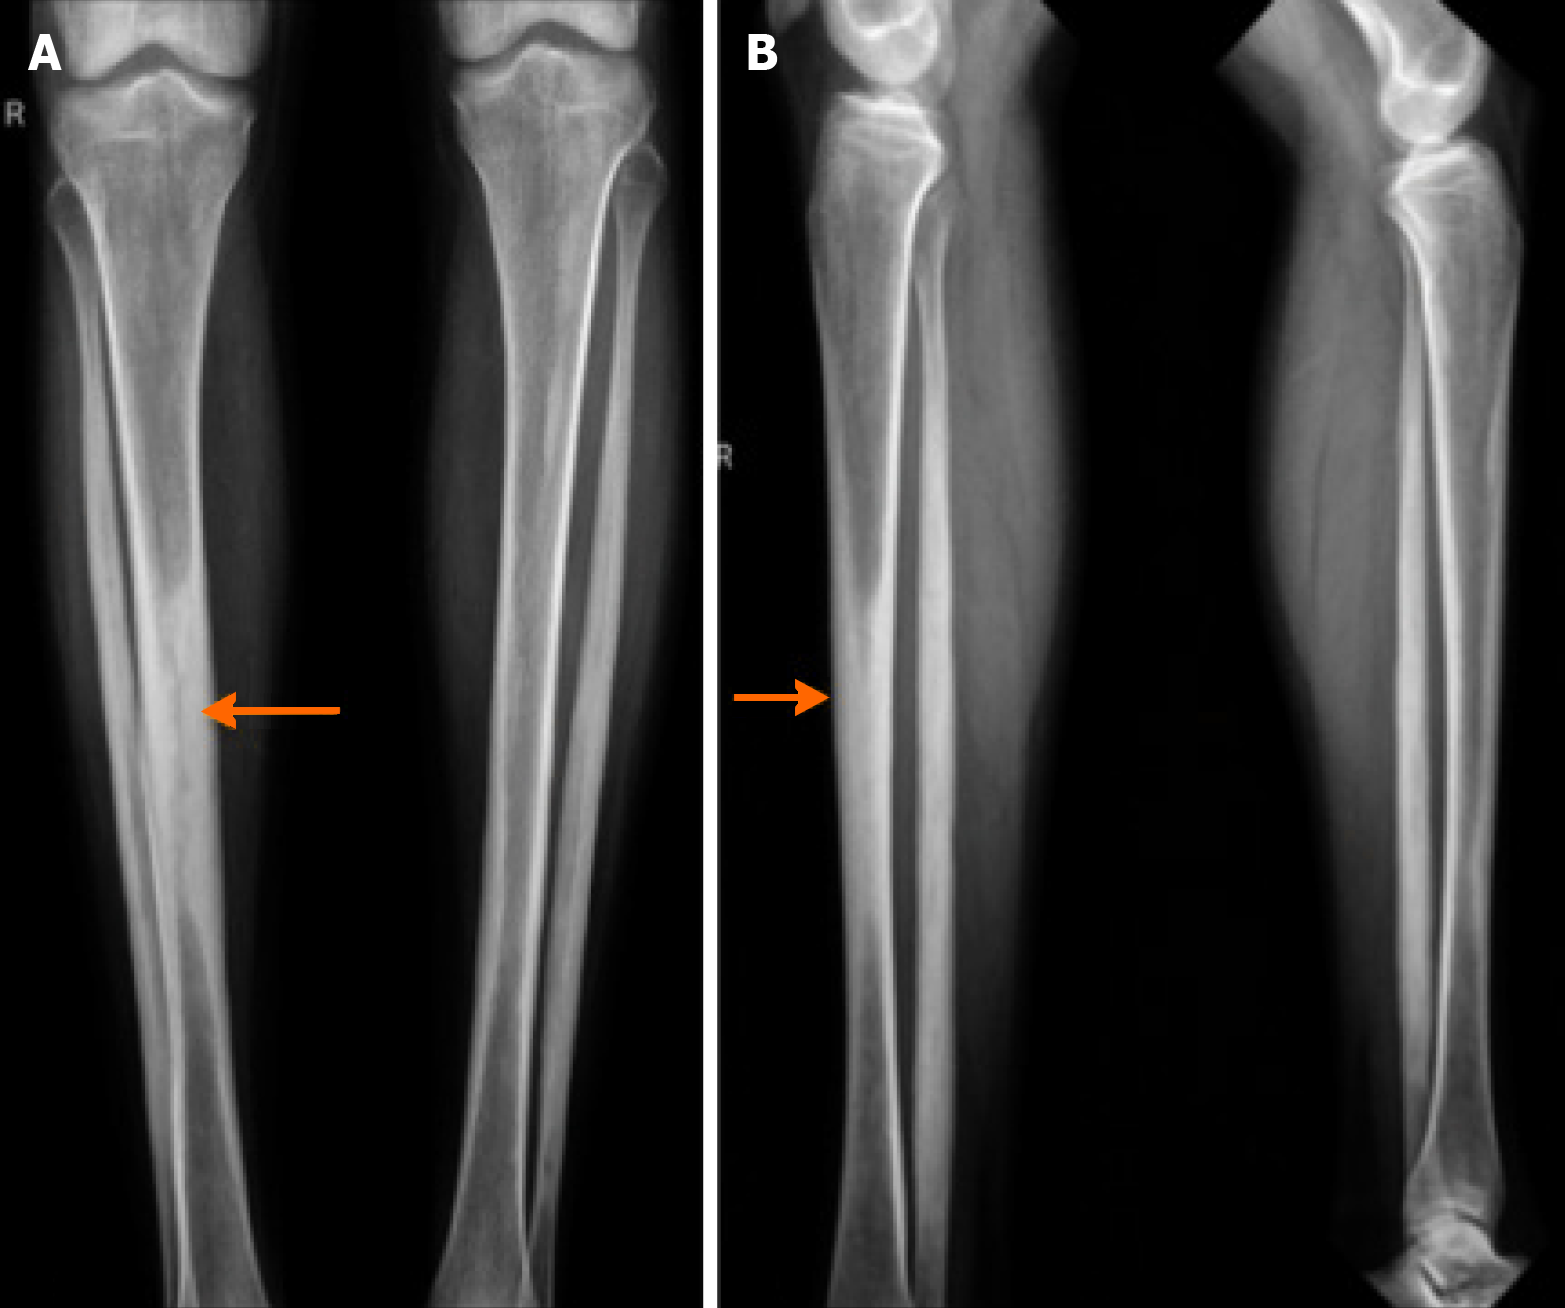

Figure 1 X-ray bilateral legs.

A and B: Anterior and lateral view showing bilateral, symmetric, osteosclerosis of the metaphyseal-diaphyseal regions (“candle wax” appearance) (arrows).